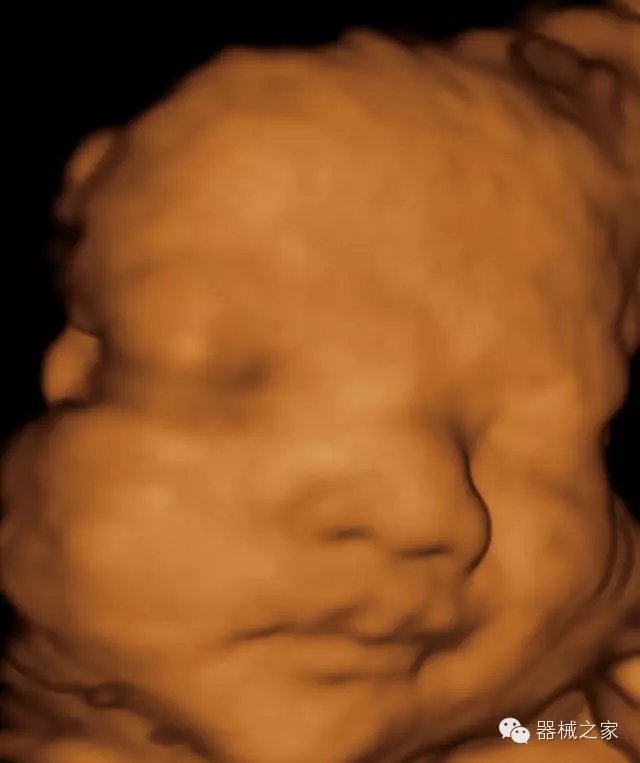

·完整的3D/4D臨床應(yīng)用,STIC, MCUT 和Auto NT等滿足產(chǎn)科所有應(yīng)用;

·更高的HQ羊膜腔鏡成像技術(shù)精細(xì)觀察每一個暗區(qū)細(xì)節(jié);

·高效3D/4D成像技術(shù):高速的4D幀頻,豐富的3D成像模式,智能斷層切片功能;